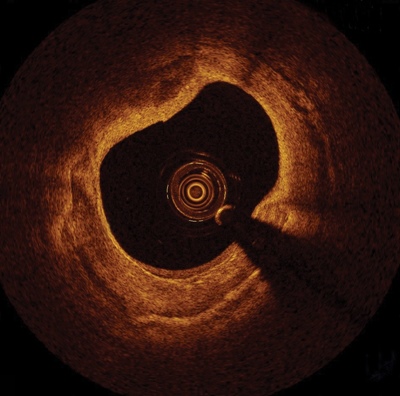

With higher resolution than earlier tools, and real-time, three-dimensional reconstruction, OCT is used to provide a 360-degree panoramic view of the blood vessel, making it easier for physicians to visualize the anatomy that they will subsequently treat with a stent.

St Jude says that the FFR and OCT measurements captured by the ILUMIEN OPTIS system allow physicians to more easily differentiate plaque build-up and determine if the narrowed arteries are causing ischemia, or a restriction in blood flow, ultimately assisting in stent placement.